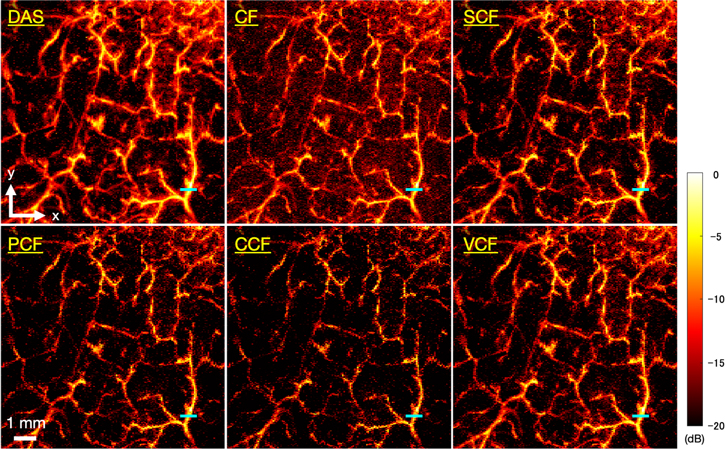

Download figure:

Standard image High-resolution imageFigure 8 shows the C-mode images of microvessels generated by each method. In the image generated by the DAS method, the running of the vessels was clear, but the vessels were visualized as being spread out. Table II shows the FWHM of the target vessel indicated by the blue line, the sharpening ratio by applying each coherence factor method to the DAS beamformed signals, and the CR and CNR calculated for each image. It could be seen that all types of coherence factors had the effect of sharpening the target vessel. In particular, the PCF method and the VCF method showed more than 20% sharpening effect and the CCF method showed 31% sharpening effect. However, in the image which applied the CF method, the CR decreased and the noise was emphasized compared to the other method. There was no significant change in the CNR between each type of coherence factor compared to the DAS method. The image obtained by applying the CCF method showed the highest CR and CNR, but the continuity of the vessels was partially lost, resulting in a rough image.

Fig. 8. (Color online) The C-mode images of microvascular imaging generated by each method.

Download figure:

Standard image High-resolution imageTable II. The FWHM of the target vessel indicated by the blue line, the sharpening ratio by applying each coherence factor method to the DAS beamformed signals, and the CR and CNR calculated for each image of microvascular imaging.

| FWHM (μm)/Sharpening ratio (%) | CR (dB) | CNR | |

|---|---|---|---|

| DAS | 233/− | 7.76 | 0.84 |

| CF | 205/12 | 6.51 | 0.88 |

| SCF | 210/10 | 8.32 | 0.86 |

| PCF | 173/26 | 9.46 | 0.92 |

| CCF | 159/31 | 10.4 | 0.93 |

| VCF | 185/21 | 8.67 | 0.89 |

5.2. Microvascular imaging of human skin

In microvascular imaging of human skin, we qualitatively and quantitatively evaluated the effects of applying five coherence factors to improve the image quality by calculating the sharpening ratio, CR, and CNR. In the same way as the phantom study, it was confirmed that the five coherence factors had a sharpening effect on the target vessel in the C-mode MAP images. The CR increased in the four coherence factors applied images and suggested an improvement in image quality except for the CF.

However, in the microvascular imaging of human skin, where the measurement range was set to 0.2–2.0 mm depth from the surface to match the thickness of the dermis layer, the maximum depth of evaluable blood vessels was only about 0.7 mm from the surface (about 5.8 mm from the annular array transducer) due to the absorption and scattering of laser in the tissue. Since the penetration depth of the laser varies depending on the optical characteristics and tissue structure of the target object, it is necessary to evaluate the imaging performance of this system in more detail using a small animal model, which is expected to enable imaging with higher penetration depth.

In this paper, we also qualitatively discussed the continuity of blood vessels. As the reason for the discontinuity of blood vessels, it can be considered that there are influences such as differences in hemoglobin concentration, blood vessels structures, etc. However, in vascular imaging, the correct vascular image is unknown, and it cannot be determined that it is the original vascular running even if the continuity of blood vessels is confirmed. In the future, it will be necessary to establish a method to quantitatively evaluate the continuity of blood vessels.

5.3. Comparative investigation of coherence factor weighting methods

Since the CF method quantifies the phase difference of the signal by the ratio of the coherent energy to the total energy of the received signal, the phase differences among the channel-domain signals were not considered accurately. In addition, each element of the annular array transducer used in this system had different sensitivity. Consequently, in the case of vascular imaging, the signal in both vessels and the background area was excessively suppressed, resulting in noise-enhanced images. Hence, the CF method was not suitable for our system.

The SCF method is a weighting function that binarizes the phase of the signal. The results of the phantom study indicated that the SCF method was effective in sharpening for B-mode images, but not effective in sharpening for C-mode images. The results in Sect. 4.2 showed that the SCF method improved the CR value of the images, suggesting that the method was effective for noise suppression against C-mode, but not for sharpening. In addition, the SCF method might cause local variations due to the phase binarization process, so that the PCF, CCF, and VCF methods were more advantageous for this system. Instead, the SCF method may be an effective method for devices that perform real-time imaging because the computational complexity of the SCF method is relatively lower than that of other coherence factors due to the phase binarization.

The CCF method had the highest effect of sharpening than the other methods in both phantom study and microvascular imaging, indicating that was the most sensitive method to phase differences. However, in the B-mode MAP images of the phantom study, the diameter of the phantom was thinner than 100 μm at all depths. Furthermore, in microvascular imaging of human skin, the continuity of the vessels was partially lost, resulting in a rough image. That was because even a small phase difference could cause excessive signal suppression in the CCF method for transducers with a small number of elements, such as the annular array transducer used in this system. In particular, in the case of microvascular imaging, the system was more influenced by the noise from the surrounding tissue, which might cause excess phase differences. 26,27) The CCF method might have a positive effect on multi-element transducers because of its high sensitivity in capturing the phase differences.

The results in Sects. 4.1 and 4.2 suggested that the PCF and VCF methods were effective methods for sharpening and noise suppression for our system. In a previous study, 18) the PCF method was reported to have no advantage over the CCF and the VCF methods as it assumes that the phase of the signal is between −π and +π, and a phase discontinuity near ±π may cause artifacts in the image. Nevertheless, such problem was not confirmed in our system performing MAP visualization, suggesting that both the PCF and the VCF methods were effective in suppressing noise components and clearly visualizing the vascular structure. In the future, it is necessary to evaluate the effects of the PCF and the VCF methods more precisely using a variety of in vivo data.

In microvascular imaging, the evaluated vessel was found to be sharpened by from 10% to 31% depending on the type of coherence factor applied to the data. The PCF and the VCF method were more effective in suppressing noise components and clearly visualizing the vascular structure than the other coherence factors.

In conclusion, among the five coherence factors tested in this study, the PCF and the VCF methods were more effective to clearly visualize the microvascular structure in terms of vessel sharpening and noise suppression performances. In the future, the DAS and PCF/VCF methods will be used to visualize the frequency-dependent anatomical vascular structure. 28–30)